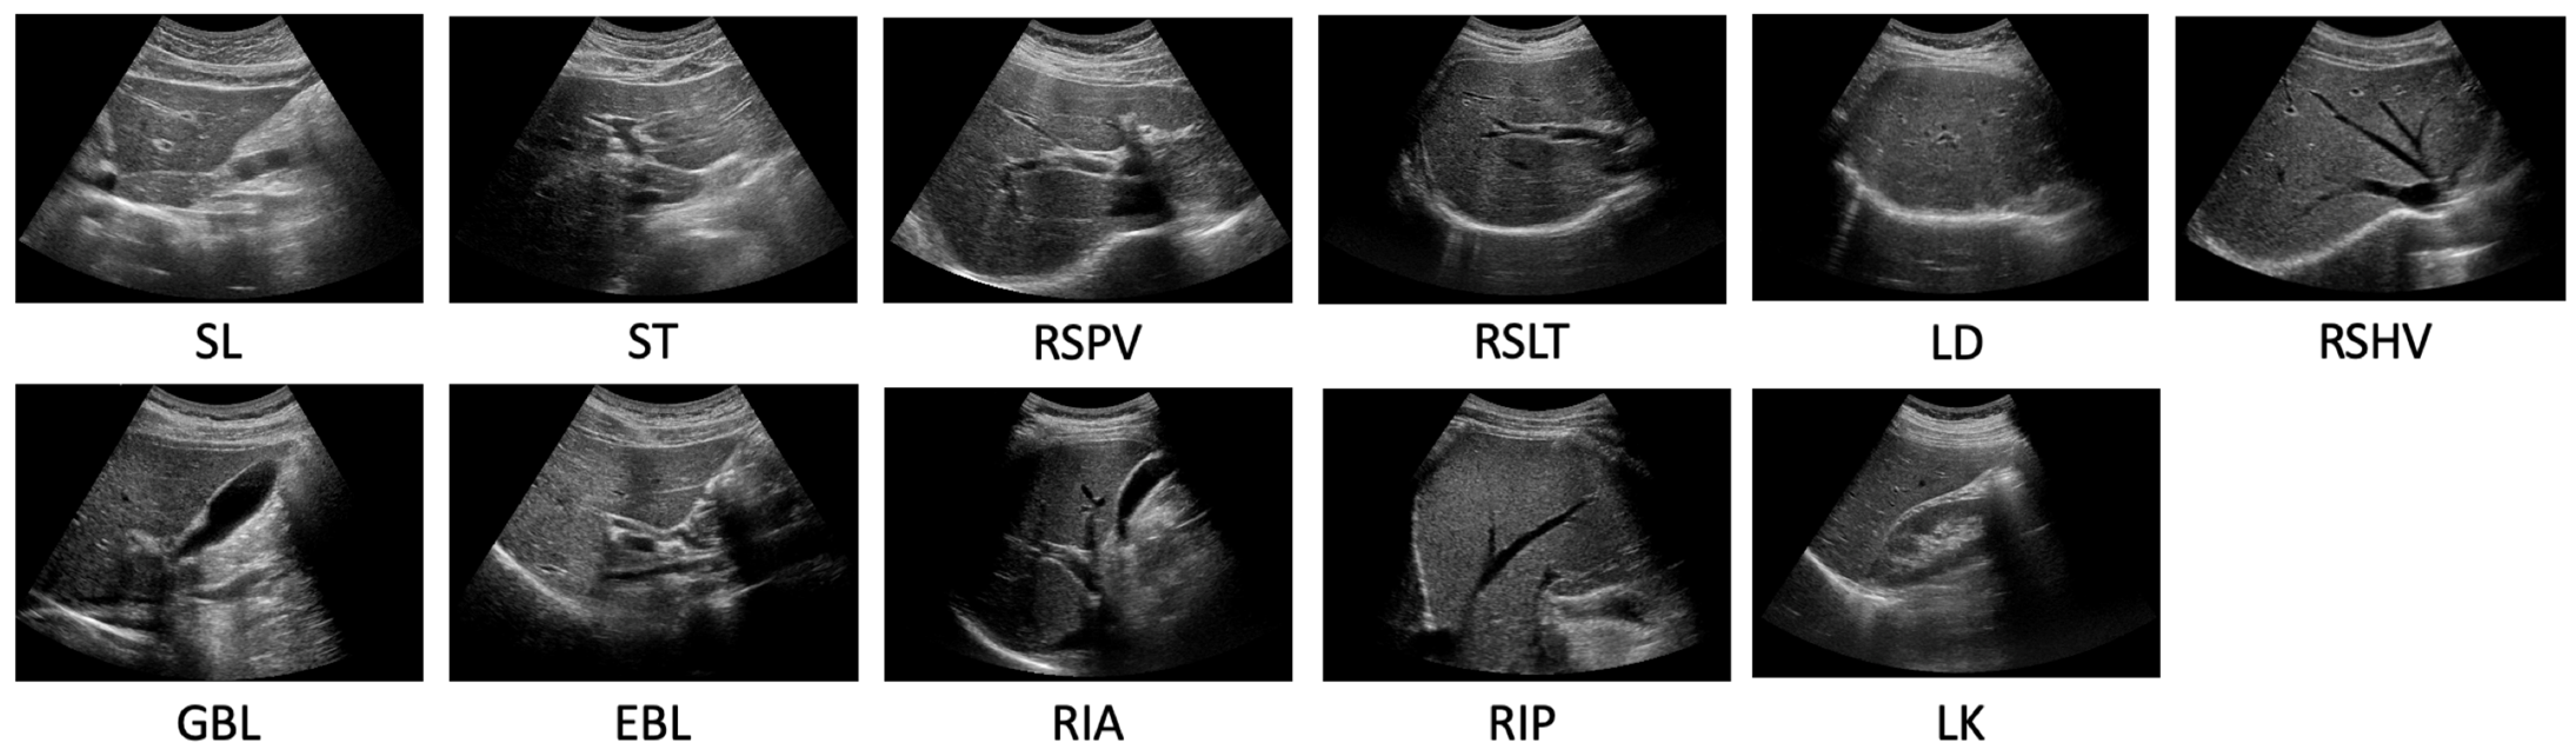

The experimental dataset for 11 standardized scanning locations estimation was composed of two primary datasets: Hospital Dataset, used exclusively for organ segmentation, and the 5 Subject Dataset. The Hospital Dataset is a subset of an ethically approved dataset from Samsung Medical Center (SMC), featuring a diverse range of patients in terms of age and gender. This dataset was acquired using five different machines, SEQUOIA, iU22, LOGIQ, HI VISION Ascendus, and EPIQ 5G. The 5 Subject Dataset was obtained by recruiting five subjects and obtaining their informed consent. Radiologists directly collected the data at the 11 scan locations: SL, ST, RSPV, right subcostal scan-right liver transverse (RSLT), liver dome (LD), RSHV, gallbladder longitudinal (GBL), EBL, right intercostal oblique scan-anterior (RIA), right intercostal oblique scan-posterior (RIP), and liver-kidney (LK), as shown in Figure 4. A specialist at SMC performed six different motions (fanning, rotating, shaking, sliding, sweeping, and compressing) on the subjects for 10–15 s at each scanning location [18], capturing the images on a LOGIQ machine to ensure a variety of appearances.

Figure 4.

Representative images of the 11 standardized scan locations used for classification. These images were captured using a LOGIQ machine and six distinct examination motions at each scanning location to ensure a diverse range of appearances.